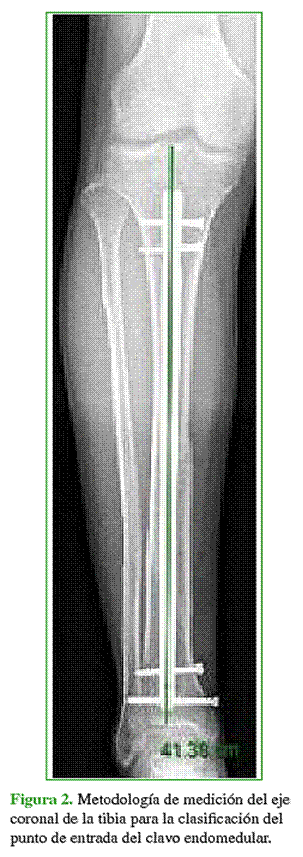

A los ocho meses de la cirugía y con las fracturas ya consolidadas, se realizó nuevamente la medición para valorar la alineación de la fractura, de la misma manera que en el período posquirúrgico inmediato; en esta ocasión, teniendo en cuenta los grados de desalineación de la fractura en el plano coronal, clasificados en: varo, valgo y neutro (Figuras 3-5).

Considerando el punto de entrada del clavo endomedular (central, medial o lateral), luego de la cirugía, la radiografía indica que, salvo el primero de estos (central), las restantes posiciones sufrieron desalineación significativa (p = 0,002 y p = 0,0011 para las mediales y laterales, respectivamente). En efecto, en el 87% de los pacientes que recibieron el clavo en la posición central, también estaba central (es decir, posición neutra) luego de la cirugía. Por el contrario, de los que recibieron el clavo en la posición medial, apenas el 3,5% se mantuvo en la posición original, ya que el 93% tuvo una desalineación o tendencia al valgo, mientras que, en todos los pacientes con punto de entrada lateral, se observó desalineación en el plano coronal, en las radiografías posquirúrgicas: el 84% de estos presentó desalineación o tendencia al varo. Este comportamiento solo se atenuó cuando la clasificación de las fracturas (AO) era 42C, y fue homogéneo en las restantes (42A y 42B, p = 0,634).

A los ocho meses de la cirugía, la valoración radiográfica tuvo una concordancia parcial (adherencia global 81%) con aquella realizada inmediatamente después de la cirugía: esto es, si bien las centrales permanecieron en esa posición en su mayoría (87% de los pacientes) y las mediales con tendencia a la desalineación en valgo (73%), de éstas, en siete pacientes (24%), se mantuvo la posición original. La Figura 2 ilustra, de manera global, este comportamiento.

Finalmente, analizando las radiografías posquirúrgicas inmediatas, como así también el control radiográfico a los ocho meses, cuando el punto de entrada del clavo fue central, hubo apenas un 0,021 de posibilidades (o 2,1%) de alguna desalineación significativa en el período posquirúrgico y luego de ocho meses. En cambio, cuando el punto de entrada fue medial, las chances de presentar una tendencia al valgo fueron superiores a 0,85 (u 85%) ya en el momento de tomar la primera radiografía posquirúrgica; y cuando el punto de entrada del clavo endomedular fue lateral, esta chance se modificó y profundizó según el tiempo transcurrido hasta la imagen radiográfica final lograda en el paciente.